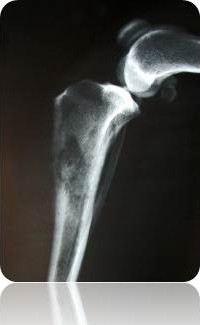

Femoral Cancer Pain

Tibial Cancer Pain